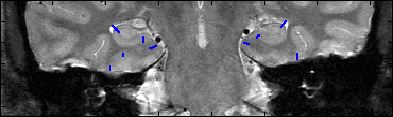

This is an example of one subjects demarcation. The A/P slice is slice

3.

3